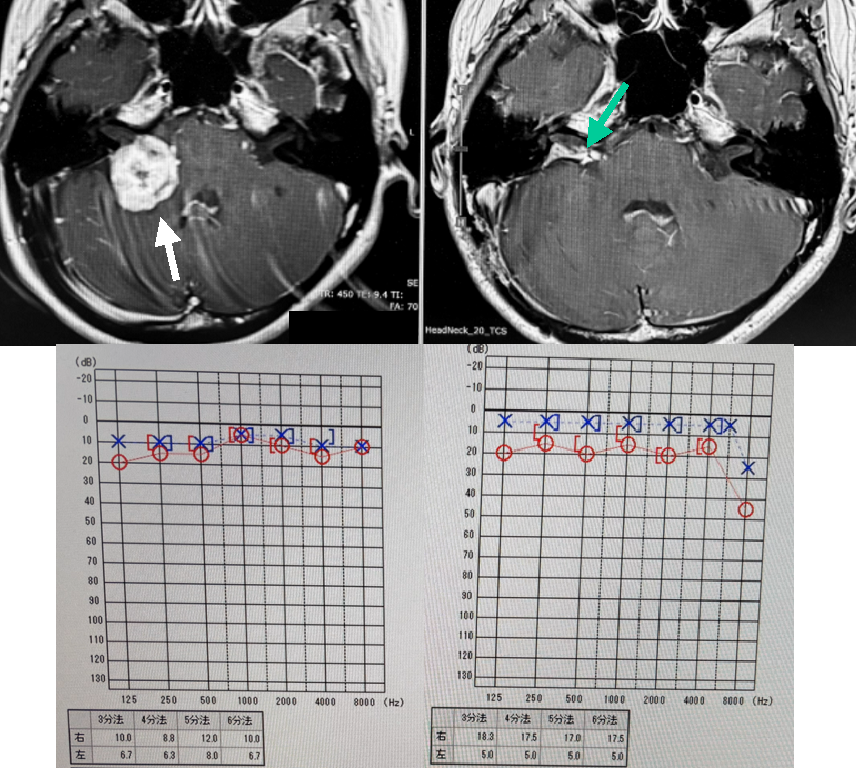

60代女性の左聴神経腫瘍です(左写真白矢印)。腫瘍が大きいために開頭腫瘍摘出を行いました。腫瘍はほとんど摘出しましたが,顔面神経との癒着が強かったごくわずかな部分を残しました。術中,0.03mAの電気刺激に対する良好な反応は維持することができ,術後に顔面神経麻痺は生じませんでした。術前有効聴力はありましたが温存できなかったため,蝸牛神経は切断して腫瘍を摘出しました。術後のMRIでは顔面神経上のごくわずかな腫瘍の残りが確認できます(右写真緑矢印)。

なお,本患者さんは腫瘍の影響で術前から水頭症を合併しており,第4脳室と呼ばれる部位の拡大がみられます(左写真赤矢印).腫瘍摘出により水頭症も改善し,術後は第4脳室も縮小しています(右写真赤矢印)。

30代女性の右聴神経腫瘍です(上段左写真白矢印)。腫瘍が大きいために開頭腫瘍摘出を行いました。この患者さんは腫瘍側の聴力が保たれていました(下段左の聴力検査結果参照。赤が腫瘍側である右の聴力です)。年齢も若いことから腫瘍摘出と共に聴力の温存も図る方針としました。腫瘍と蝸牛神経,顔面神経の癒着が比較的強かったため,神経上に薄く一層の腫瘍を残存させました. 術中,0.03mAの電気刺激に対する良好な反応を維持することができ,術後に顔面神経麻痺は生じませんでした。術後のMRIでは神経上に残したわずかな腫瘍が確認できます(上段右写真緑矢印)。術後の聴力検査では,高音域でわすかな低下がみられますが,ほぼ術前と同程度に聴力は保たれています(下段右の聴力検査結果参照.赤が腫瘍側である右の聴力です)。 残存腫瘍に対しては半年ごとのMRIによる追跡を行い,増大傾向がみられれば,ガンマナイフを検討する方針としています。